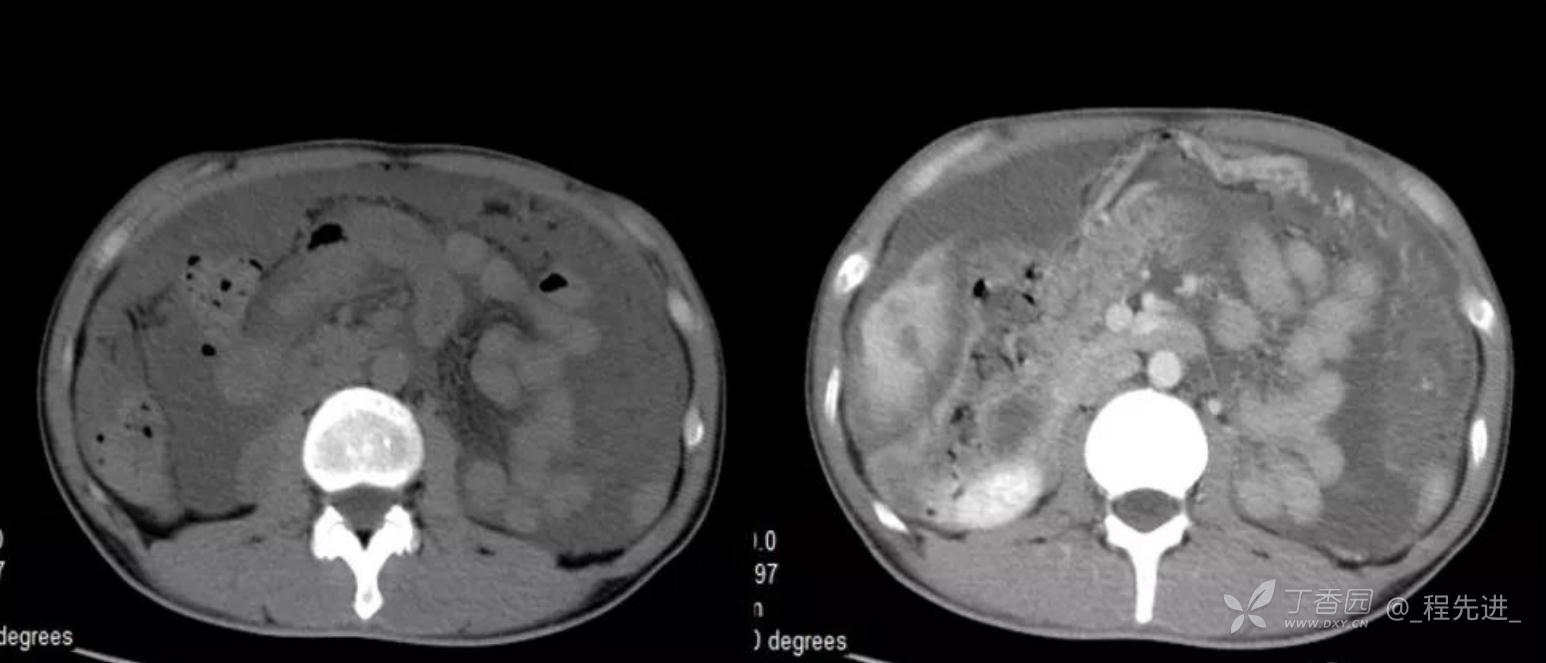

患者性别:男

患者年龄:46岁

主诉:腹胀10余天

现病史:患者10余天前无诱因腹胀,进食后加重,便后缓解,余无特殊

腹膜假黏液瘤 (5)